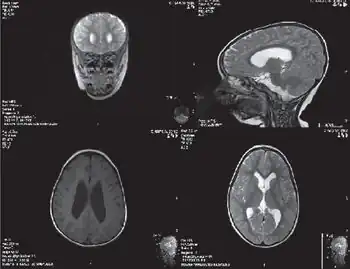

| Cranial MRI image of individual with Emanuel syndrome | |